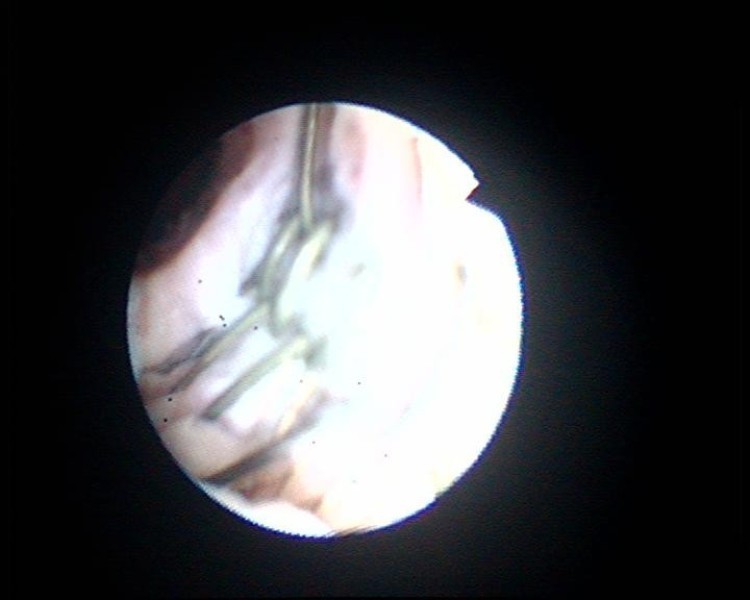

Figure 5From: Lessons we learn from review of urological procedures performed during three decades in a spinal cord injury patient: a case reportFlexible cystoscopy shows naked wires of UroLume stent. These wires are not covered by urethral mucosa.Back to article page